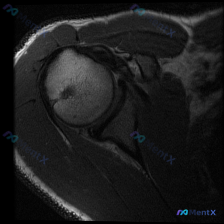

肩部MRI提示盂唇无明显异常,持续性肩痛还可能是什么原因?

最近看到一个肩部MRI病例,资料里只有T1序列冠状位影像。影像分析显示:肱骨头、肩胛盂形态正常,冈上肌腱走行连续无撕裂,上方盂唇呈三角形低信号、轮廓规则,未见明显的信号异常或撕裂征象。

虽然影像没找到盂唇的结构性病变,但患者很可能有持续性肩痛症状(不然也不会做MRI)。大家第一眼看到这种情况,会先往哪个方向考虑呢?